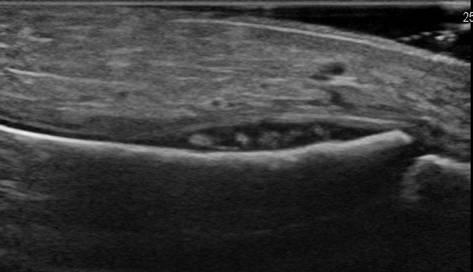

Tụ mủ dưới màng xương

Viêm xương tủy

» Thông tin: Nam giới – 11 tuổi.

» Lâm sàng: Sưng đau cẳng chân.

# Tụ mủ dưới màng xương.